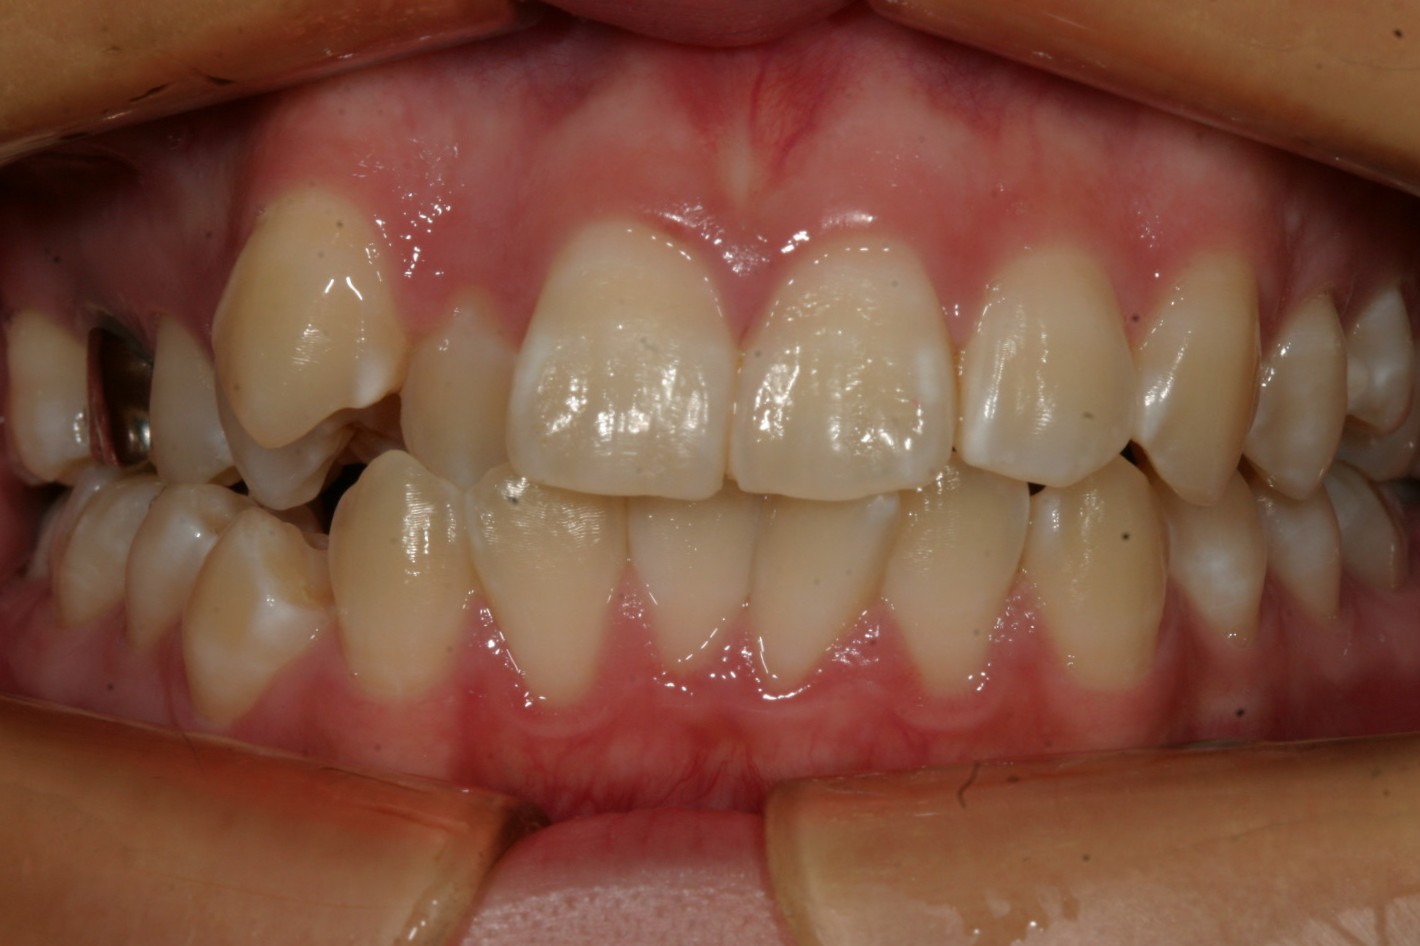

右の八重歯が気になる。

右の八重歯が飛び出してるのが気になりますね~

下の前歯もガタガタです。

側面観もガタガタしています。